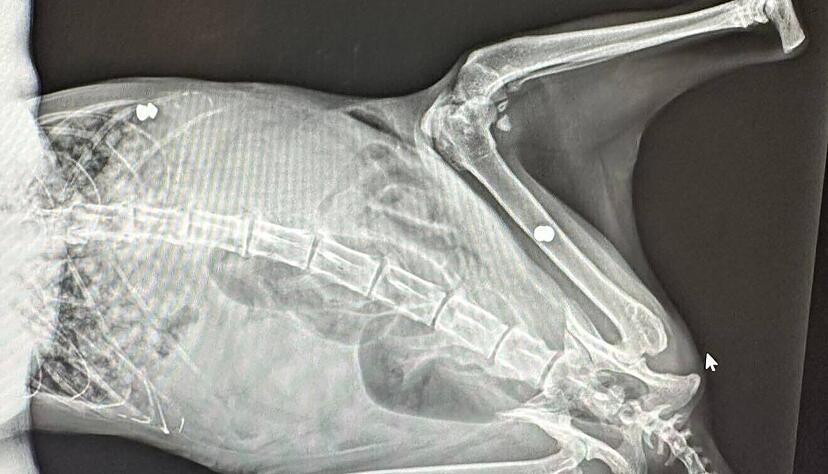

Auf Röntgenbildern wird dann sichtbar, dass sich zwei Projektile in den Körper der Katze gebohrt haben: Auf der rechten Körperseite auf Brusthöhe sowie im rechten Oberbein steckt jeweils ein 4,5 Millimeter großes, spitzes Projektil.

Für Bernhard Klier, Gründer der Tierrettung Odenwald Hohenlohe, ist damit klar: Jemand hat mit einem Luftgewehr zwei Schüsse auf die Katze abgegeben. „Das ist nicht das erste Mal, dass ich so etwas als Tierretter sehe.“

Die verwendeten 4,5 Millimeter starken Diabolo-Projektile werden laut Tierretter Klier von Privatpersonen genutzt. Sportschützen würden dagegen Geschosse mit flacher Spitze nutzen, weil diese ein besseres Loch in die Zielscheibe stanzen. Die Projektile bestehen aus Blei, was für Tiere gesundheitsschädlich ist.